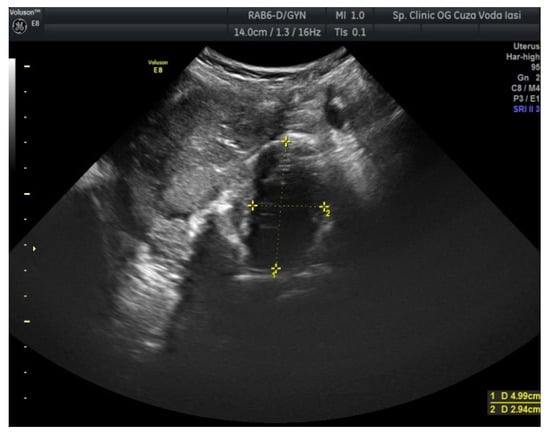

2. Case Presentation